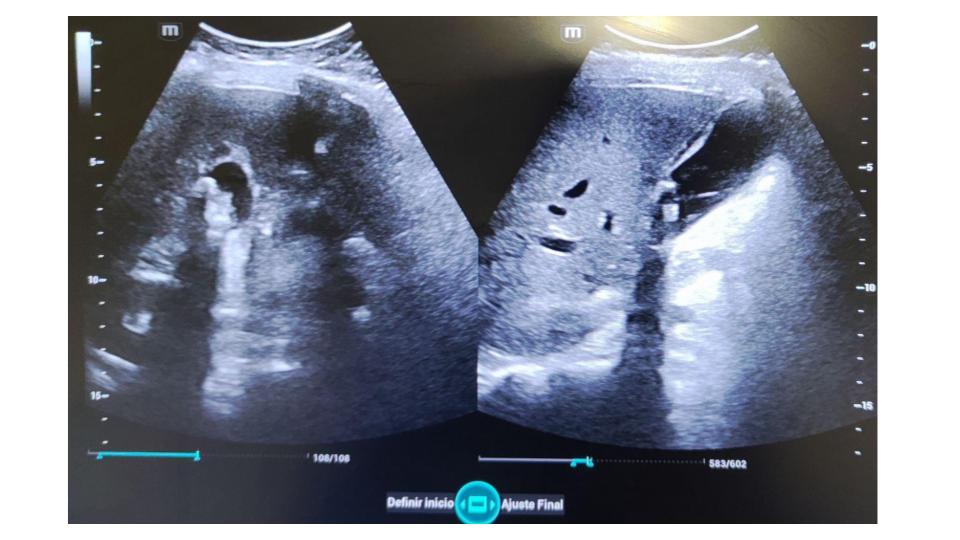

Ecografía a pie de cama con sistemática de exploración: Expansión anormal del conducto pancreático (conducto de wirsung), vía extrahepática con ligera dilatación sin imágenes patológicas en su luz. Vesícula biliar imágenes hiperecogénicas múltiples en su interior, que sugieren litiasis biliar y paredes vesicales engrosadas sin edema perivesicular.

BISAP Score en las primeras 24 horas, 3 puntos y criterios de atlanta moderado. Por lo que se orienta como dolor abdominal obstructivo, pancreatitis aguda (PA) de alto riesgo y elevada mortalidad.

La obstrucción pancreática es la causa principal de bloqueo en el flujo normal del jugo pancreático. Un wirsung que está dilatado por encima de 2 mm requiere evaluación más intensiva y tratamiento cuidadoso por alta sospecha de carcinoma pancreático.